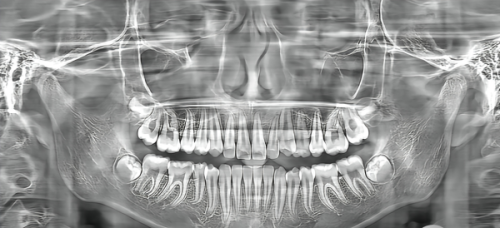

在牙科健康方面,特别多人都存在着不少痛点。牙齿不齐影响美观,让人在社交场合缺乏自信;牙疼起来更是要命,重度影响生活和工作;牙齿缺失不仅影响咀嚼功能,还可能导致面部变形。而且,面对众多的口腔门诊部,患者往往会陷入选择焦虑,担心遇到不专精的医生,治疗成效不佳,甚至还可能出现医疗事故。